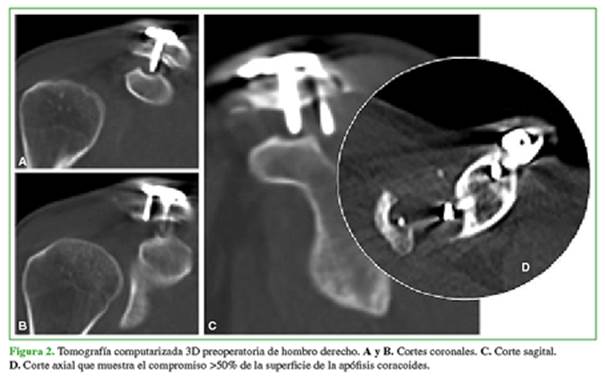

Luego de los estudios complementarios, se programó la cirugía de extracción de la osteosíntesis a los 15 días de la consulta inicial. Para el retiro de la placa y los tornillos, se efectuó un bloqueo plexual selectivo y se administró sedación. Se colocó al paciente en posición de silla de playa. Se realizó el abordaje por sobre la incisión previa y se extrajo el material de osteosíntesis bajo visión directa. Se solicitaron radiografías de control posoperatorio que resultaron satisfactorias (Figura 3). Un mes después de la cirugía, el paciente ya no sentía dolor y el rango de movilidad activo era completo, por lo que fue capaz de reanudar sus actividades de la vida diaria y deportivas. Fue dado de alta a los tres meses de la cirugía. La evaluación clínico-funcional a los 12 meses de la intervención incluyó la escala de Constant y la escala analógica visual para dolor. Los resultados obtenidos fueron 96 y 1/10, respectivamente. No se detectaron complicaciones posoperatorias.